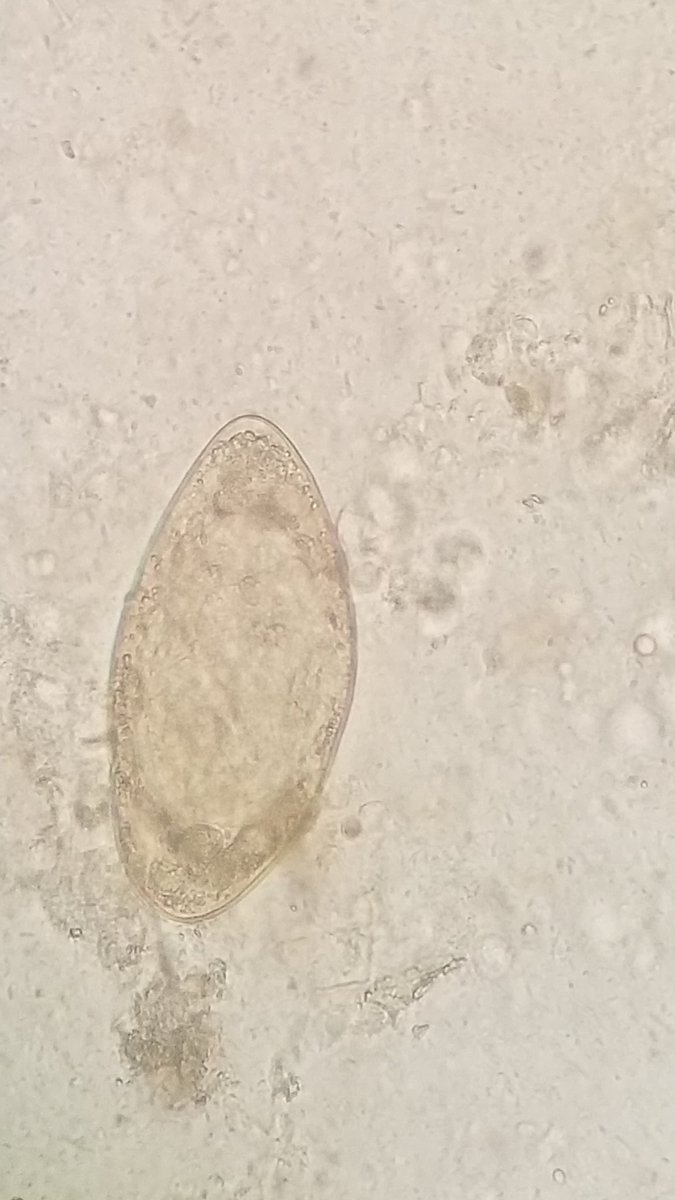

Schistosoma mansoni ova

لو تسأل فين الشوكة تبعها...؟!

بعض الاحيان يحصلها انكسار لذلك تظهر كما في الشكل 👆👆